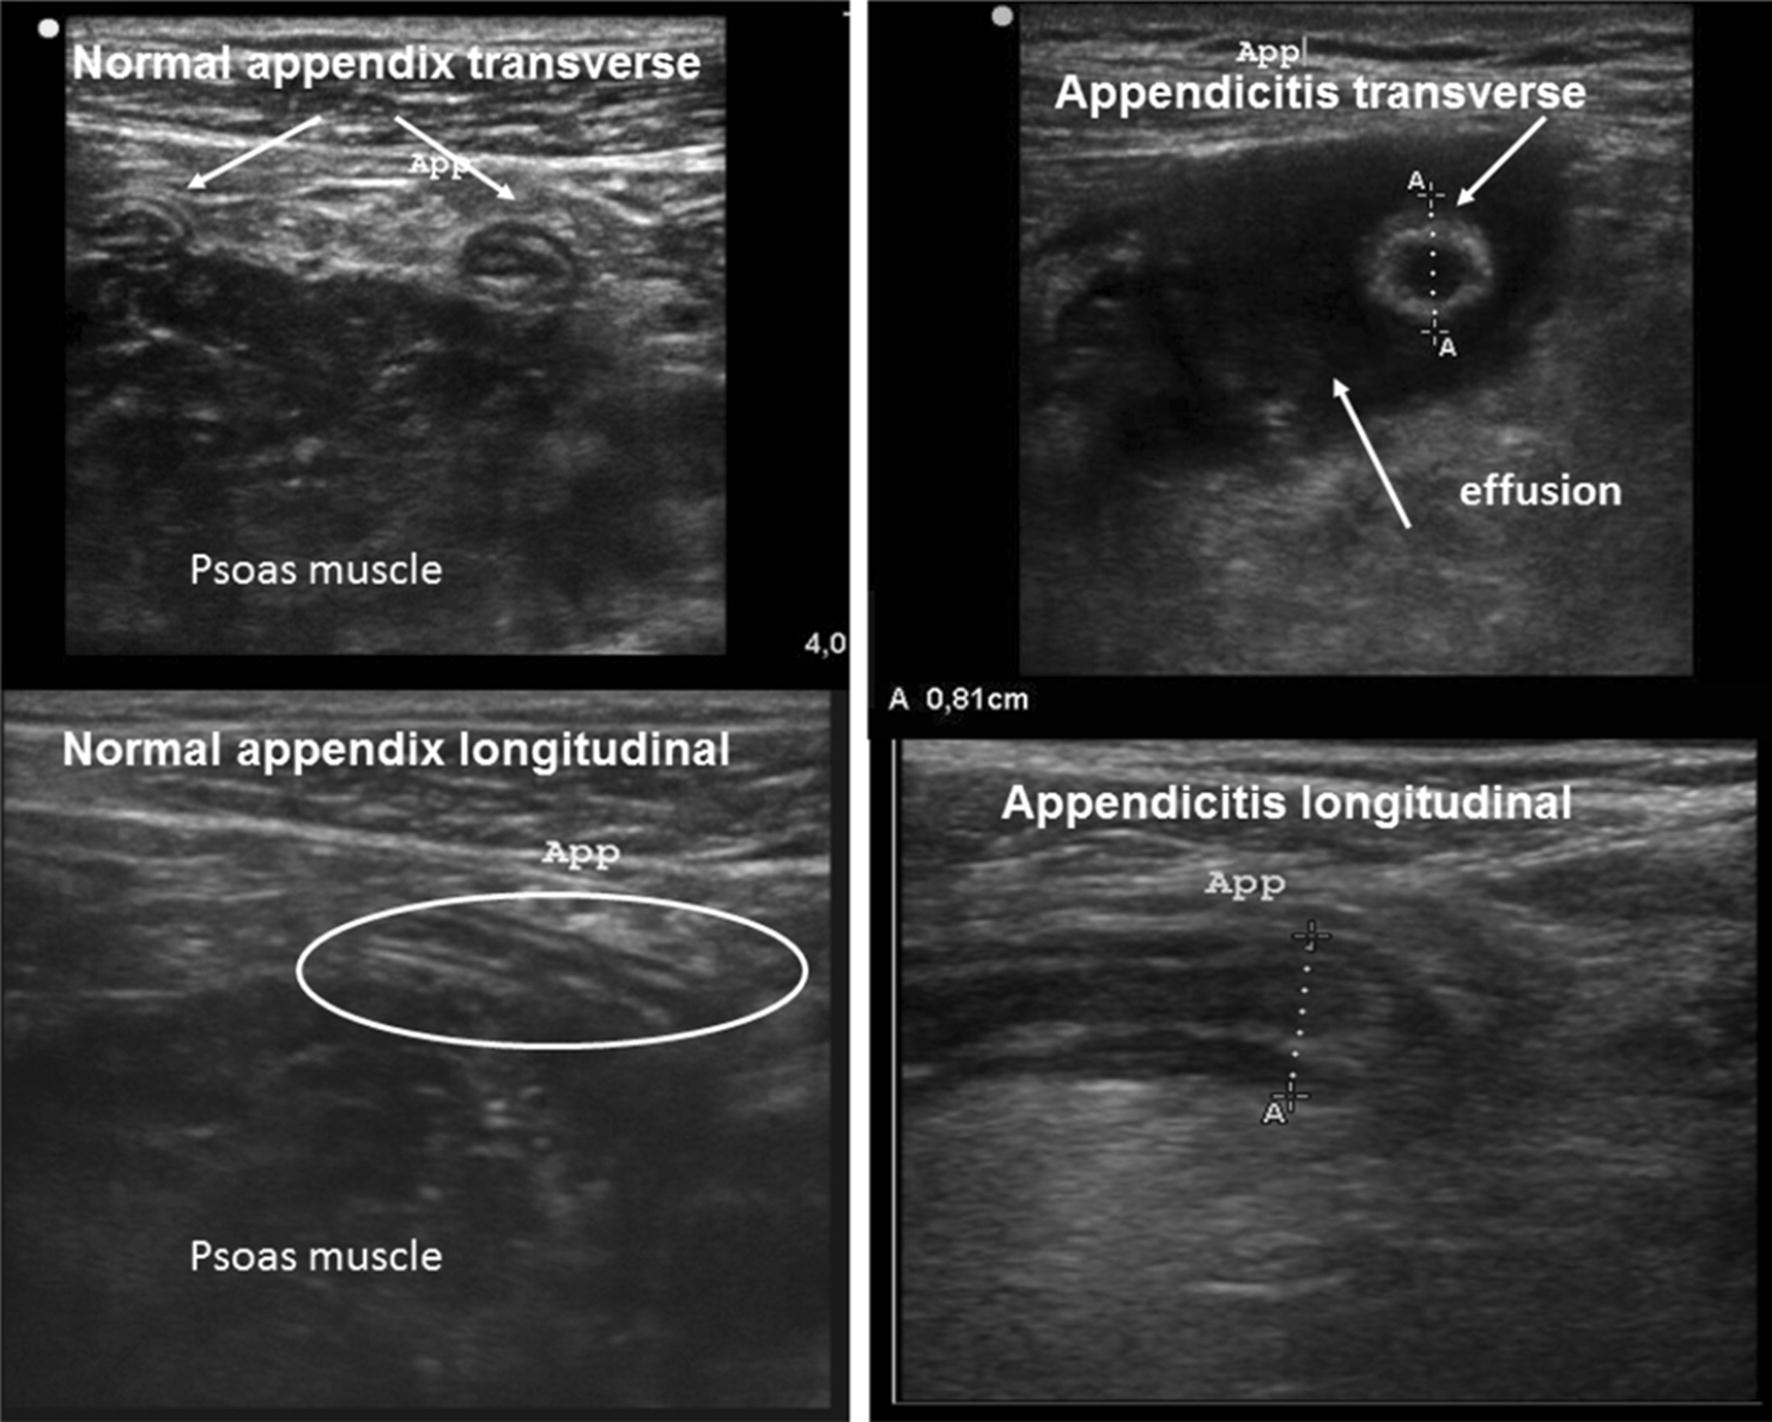

In all cases, the emergency physician attempted to adequately discern the appendix. A diagnosis of appendicitis was made in conjunction with more than two of the following images: a double cockade cross-sectional appearance of the appendix of more than 6 mm in diameter, ending as a sleeve in a longitudinal section, a non-compressible nature, and association or not of a peri-appendicular effusion. In case of normal appendix viewed (none of previous images), this diagnosis was excluded (Fig. 2).

Fig. 2.

Ultrasound appearance of a normal appendix and a pathological one